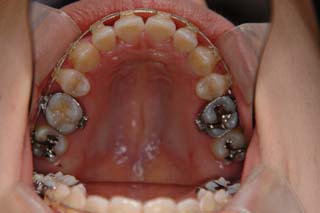

使用した主な装置名:TPB、マルチブラケット装置、オーソアンカー SMAPシステム

上顎前歯、下顎前歯の前突が見られます。大きな叢生は見られませんが、上下の口唇前突感も伴います。このような不正咬合を上下顎前突と言います。審美的な事もさることながら、歯軸の傾斜の問題から歯にかかるベクトルが良くない事、口唇の筋肉の緊張を強いるような不調和を示す事などから、不正咬合の一つとして考えられています。上顎前突傾向も伴っていますので、積極的に上顎前歯の後退を行う目的で、上顎に固定源となる 目的外使用の オーソアンカー SMAPシステム を装着しました。現在では、歯科矯正用アンカースクリュー(デュアルトップオートスクリュー、ISAアドバンスなど)といった、医療機器認証番号がある製品を用いることが多くなりました。

最終仕上げの段階です。かなり太めのワイヤーが入っていますが、このワイヤーの後にオーバーコレクション(元々の歯の捻れが有った場合、後戻りで出てきやすいので、わざと過剰に捻れを治しておく事)を行うための、細めのワイヤーを使う事もあります。